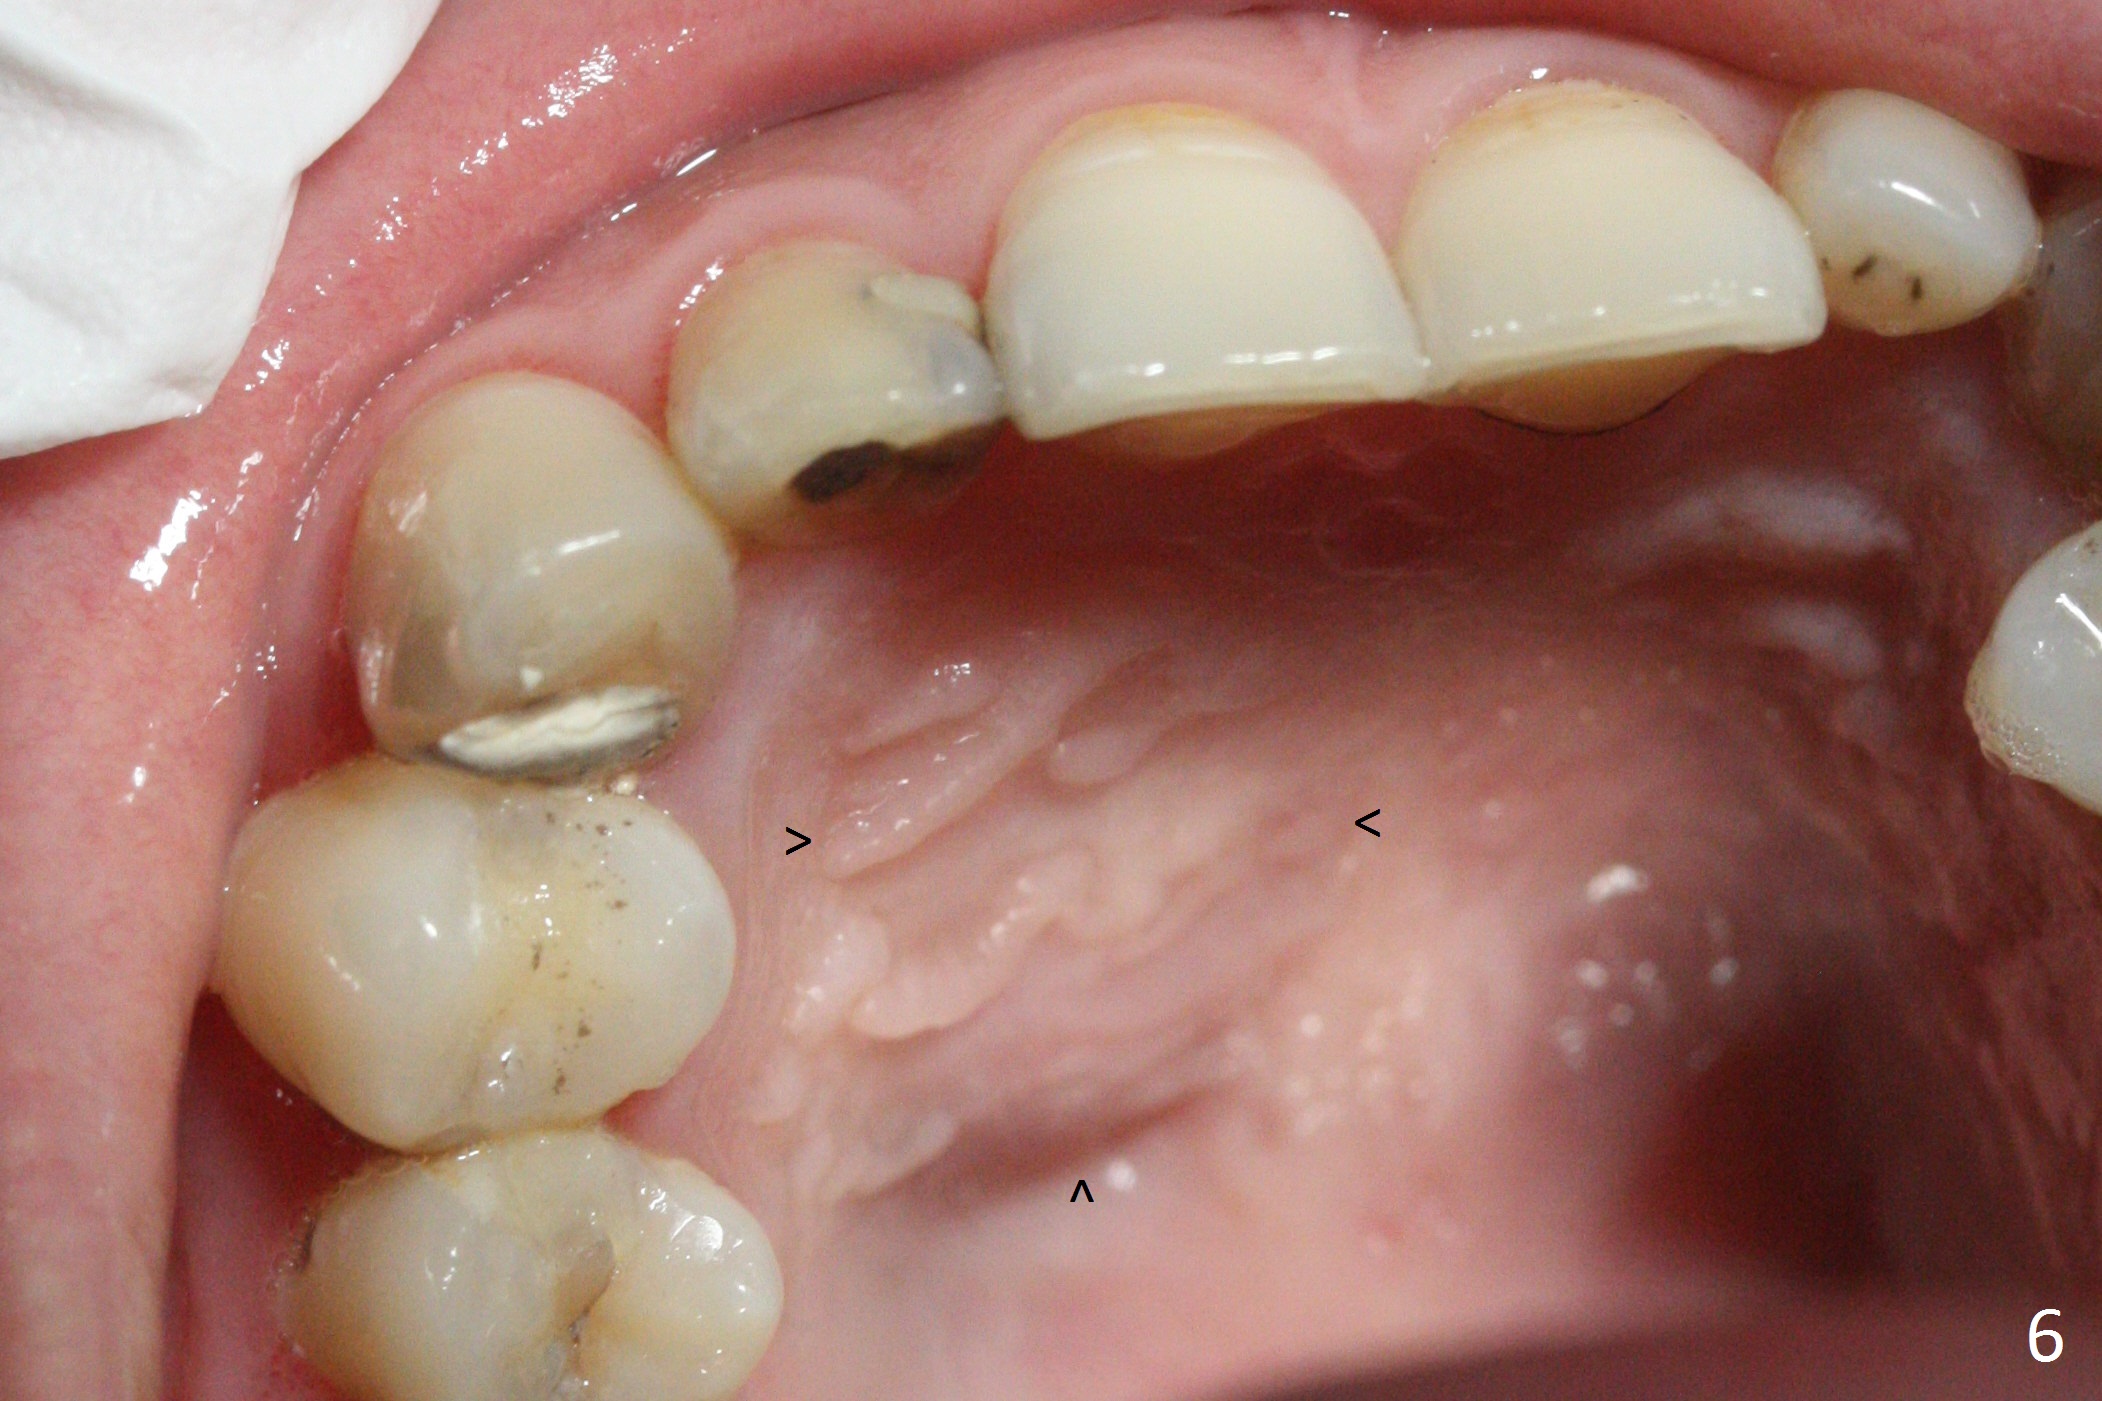

When this patient returns with improvement of symptoms, RCT will be finished. In fact the swelling relapses a month later (Fig.6). After discussion of possible cyst enucleation and increase in debridement from 30/.04 to 40/.06, a master cone of 40/.06 is inserted (Fig.7) and RCT is finished (Fig.8). Although the patient reports relapse of swelling, the palate looks normal and bone density increases 7 months postop (Fig.9). For 14 implant placement, CT is taken 2 years 1 month post RCT (Fig.10,11). Radiolucency is confined to the apex of the tooth #7 (white *). The labial concavities mesial and distal to the left lateral incisor makes radiolucencies (bone loss) look more radiolucent, creating globumaxillary cyst image. The globumaxillary cyst is a terminology for its shape. It does not mean congenital in nature. The treatment is dependent upon vitality test of the involved teeth.